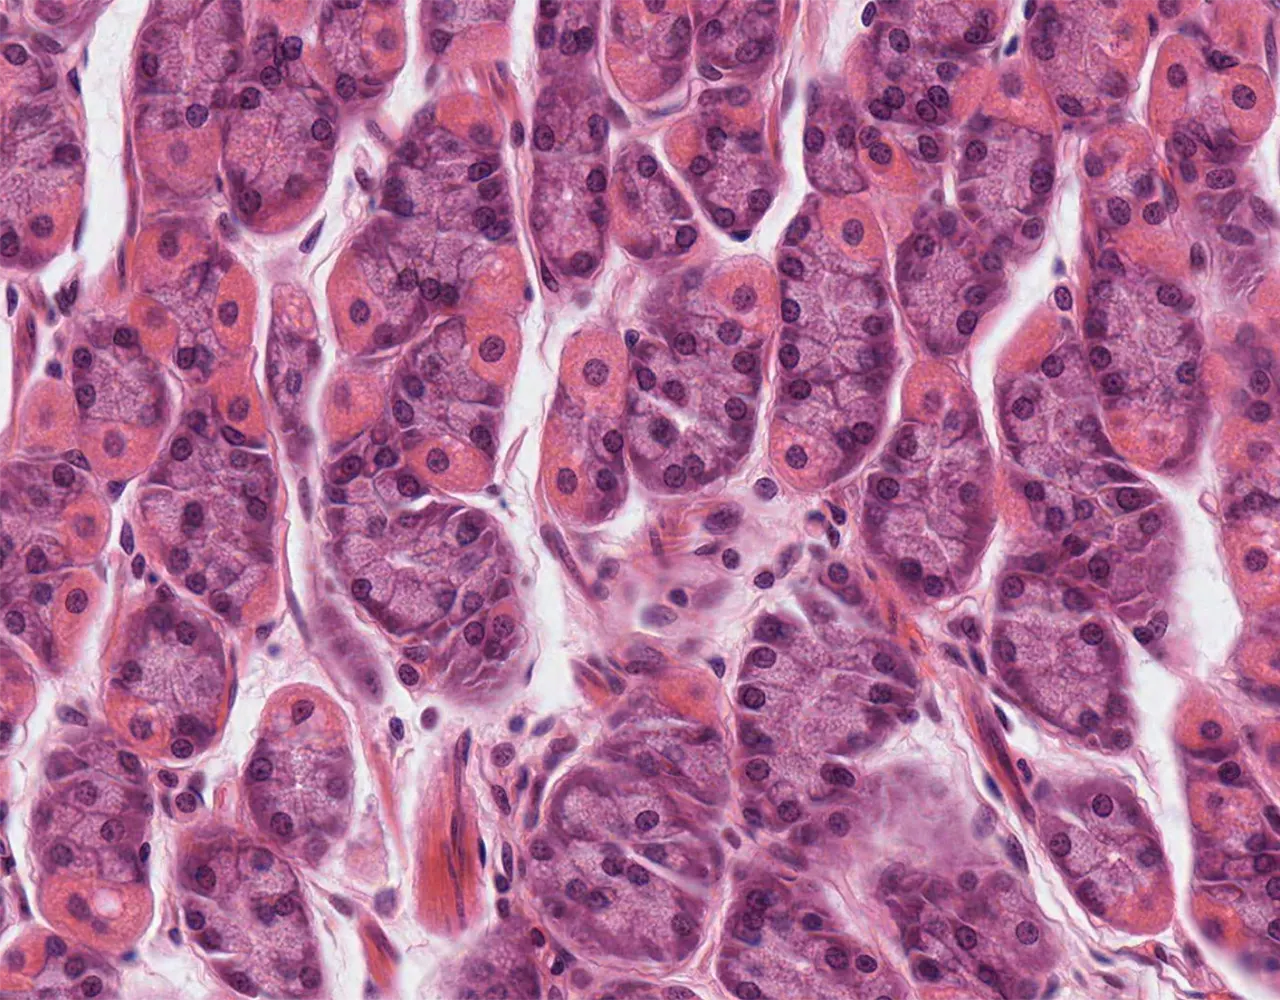

- The wall of the stomach is composed of four layers, from the innermost to the outermost: mucosa, submucosa, muscularis propria, and serosa.